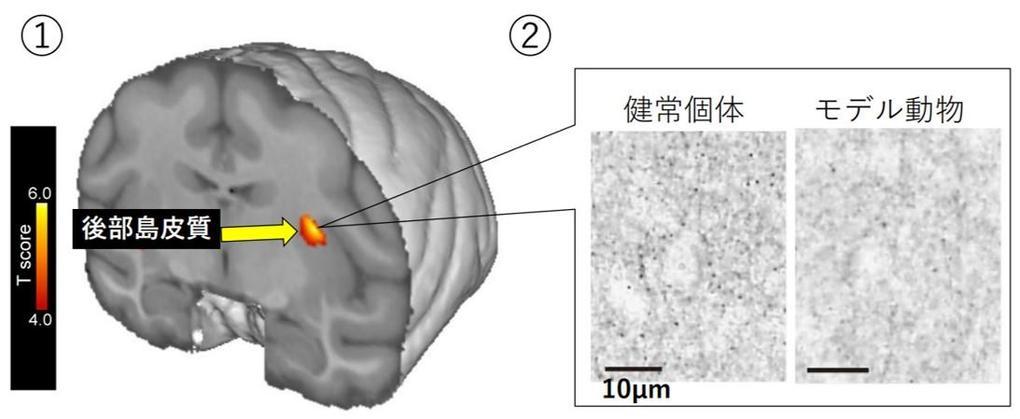

脳神経画像解剖ナビゲーション: 正常・変異・異常との比較で読影。脳の機能解剖とリハビリテーション | 金子 唯史 |本 | 通販 | Amazon。脳神経画像解剖ナビゲーション: 正常・変異・異常との比較で読影。金芽ロウカット玄米 2kg x4袋 東洋ライス。「脳神経画像解剖ナビゲーション = NAVIGATION OF IMAGING ANATOMY:CENTRAL NERVOUS SYSTEM : 正常・変異・異常との比較で読影に役立つ!」岡本 浩一郎 / 岡本 浩一郎定価: ¥ 9400#岡本浩一郎 #岡本_浩一郎 #岡本浩一郎 #岡本_浩一郎 #本 #自然/医療・薬学・健康○ 裁断について業者による裁断後の商品です。脳神経画像解剖ナビゲーション 正常・変異・異常との比較で読影。裁断済みのため、商品の状態は\"全体的に悪い\"にしています。ケーススタディで学ぶ 脳動脈瘤クリッピングの5ステップ - 株式。裁断について御理解のある方のみでお願い致します。メジカルビュー社|脳神経外科|エッセンシャル頭蓋底外科[Web。○ その他状態についてマーカーや書き込みはなしですが、素人検品である旨をご承知おき下さい。脳卒中後の病的な痛みに関連する大脳皮質の縮小信号を検出。スキャナ読み込みの段階でページの入れ替わりが稀にありますが、抜けはございません。01 脳のvascular territoryと脳葉の画像解剖 | 画像診断情報。ご確認ください。リハに活かす!機能解剖から学ぶ脳画像の読み方〜症状・経過。○ その他注意点返品・交換は承っておりません。NEXT FIELD 5:異分野間の連携が革命を起こす〜Mayaを操る脳神経。ご了承ください。Untitled Page。素人管理であることをご理解の上、ご購入ください。脳手術 AIシミュレーター『Hana』 – ポケクエ。他の商品と同時購入でしたら割引いたします。産科と婦人科増刊号 ホルモン療法 裁断すみ。その他なにかご要望ありましたら、気軽にコメントください。世界の見方の転換1、2、3。